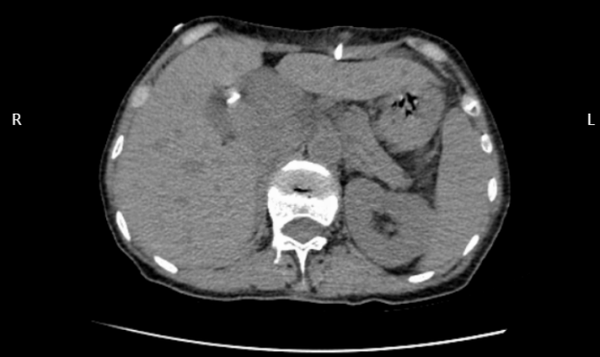

治療方案確定后,為患者實(shí)施微創(chuàng)膽道置管引流術(shù)。在床旁超聲引導(dǎo)下,成功穿刺達(dá)擴(kuò)張的膽管,置入導(dǎo)絲,引入引流導(dǎo)管,妥善固定,完成手術(shù)。手術(shù)過(guò)程中,患者生命體征平穩(wěn),穿刺置管順利,達(dá)到預(yù)期目的。

術(shù)后CT顯示引流管準(zhǔn)確置入擴(kuò)張的膽管